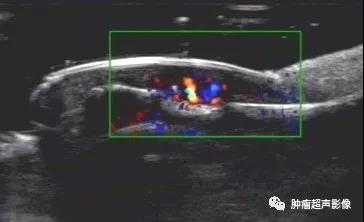

超声表现:一般呈低回声(少部分为高回声,胃血管球瘤一般都呈高回声,类似肝脏血管瘤表现),多为类圆形或椭圆形,边界清,较大肿瘤可显示其对指骨的侵蚀,内部及周边血流丰富,典型的呈花环状或小火球样,频谱呈低速低阻。

左甲下疼痛,超声显示低回声,边界清,椭圆形,后方指骨凹陷,血流丰富。呈现典型血管球瘤表现。